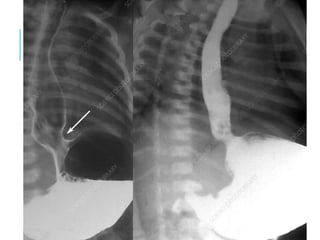

PHARYNX AND ESOPHAGUS

ZENKER’S

DIVERTICU

LUM

OESOPHAGEAL

REFLUX